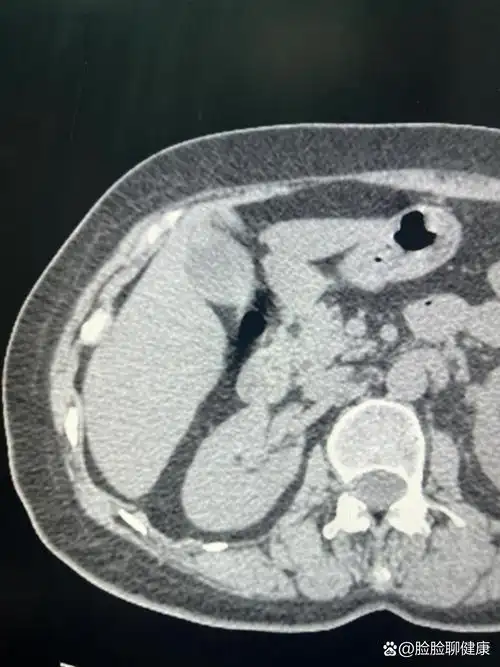

节段型胆囊腺肌症伴结石

胆囊腺肌症一例

胆囊底部局限性增厚:胆囊腺肌症

胆囊腺肌症